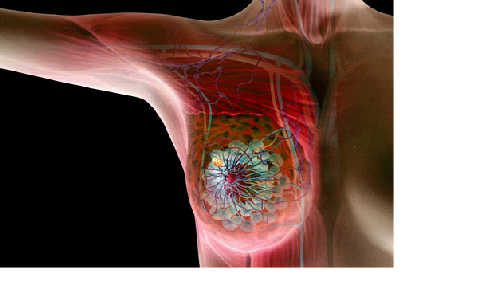

Meme kanseri tanısı konan hastalarda tümörün boyutları ve ne kadar yayılmış olduğunun araştırılması gerekir. Bu işleme EVRELEME denmektedir.

Evreleme işlemi sırasında kanserin sadece memede olup olmadığını, yakınlardaki ( koluk altı gibi ) lenf bezlerinde yayılım olup olmadığı ve akciğer, karaciğer gibi organlara yayılım yapıp yapmadığını tanımlamak için 0-IV evreleme skalası kullanılır.

Meme kanserinde evrelemenin önemi tedaviye karar verirken kendini göstermektedir. Evreleme sayesinde ne tür tedavilere ne kadar süre ile devam edileceğine karar verilmektedir.